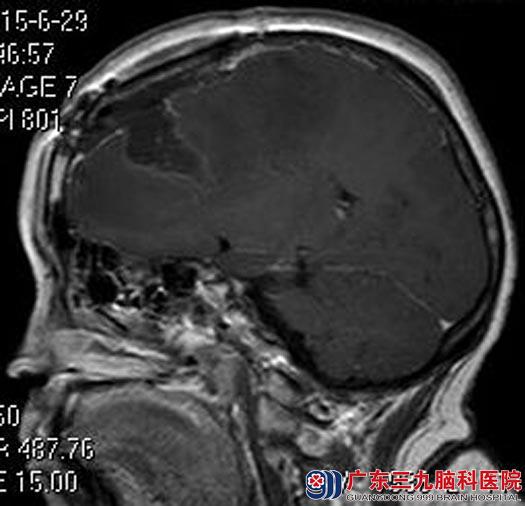

完善相关检查后,由综合神经外科的鲁明主任主刀,在全麻下行左侧额部脑膜瘤切除术,术前导航定位肿瘤及脑膜强化征标记,术中再次导航,显微镜下见肿瘤周围三条回流静脉存在,肿瘤质地中,血供较丰富,予肿瘤全切,手术顺利。雪姨已康复出院。术后病理结果:过渡型脑膜瘤(WHO I级)。